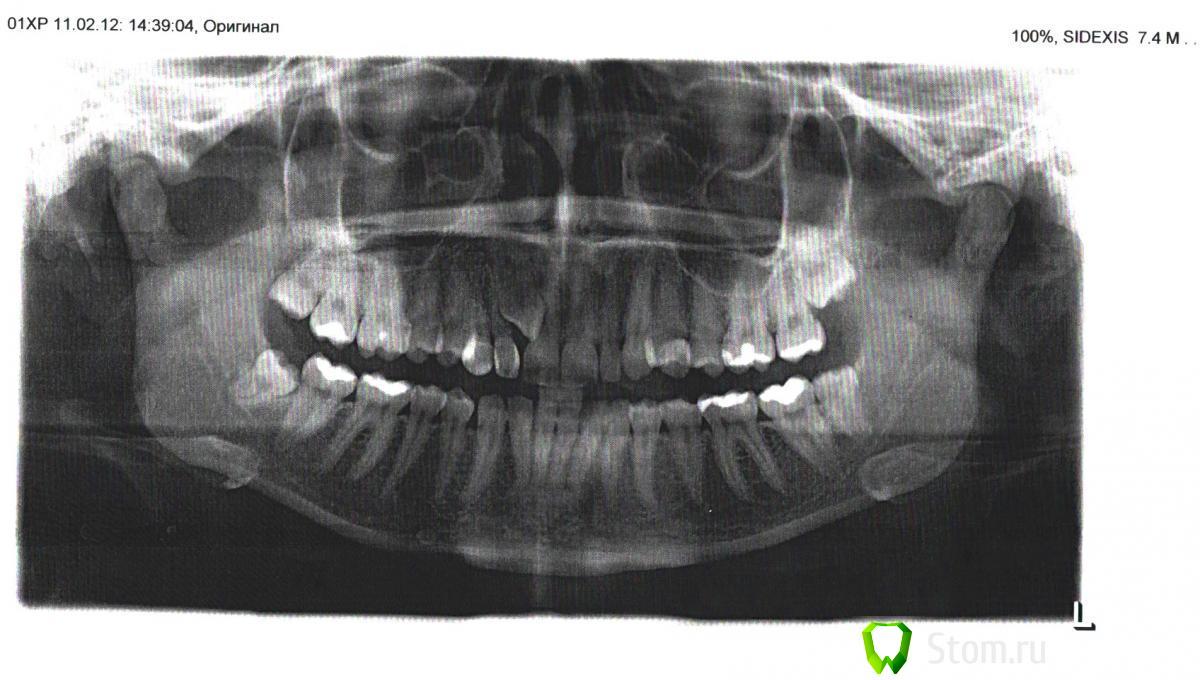

irina_kn Опубликовано 6 апреля, 2012 Поделиться Опубликовано 6 апреля, 2012 Здравствуйте! У меня тут такое дело, из неба начал резаться зуб, всегда была припухлость на этом места, и ни один стоматолог ни разу не сказал, что там зуб. Была во многих клиниках и почти все говорят, что придется клык удалять и вытягивать этот зуб на его место, ставить скобы где-то на пол года. Скобы для меня сейчас не вариант, поэтому я в ужасе. И не понимаю, как его можно вытянуть на место клыка, т.к растет он далеко от него, и он развернут. Один врач сказал, что его можно удалить из неба, но он опасается, что молочный зуб со временем рассосется и на его место не получиться вставить имплант. Ссылка на комментарий